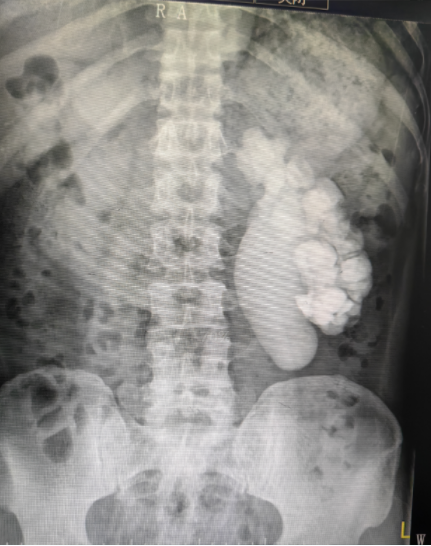

術(shù)前CT影像

52歲的謝大叔因“反復(fù)左側(cè)腰痛1年”曾到某三甲醫(yī)院就診治療,后病情反復(fù)一直不見好轉(zhuǎn),在聽聞我院有省級醫(yī)院專家坐診的消息后,決定抱著試一試的心態(tài)來到我院。謝富彬醫(yī)生接診,充分理解大叔內(nèi)心的憂愁,立即為其完善相關(guān)檢查,且安慰謝大叔“不必過于憂愁,在省級醫(yī)院專家教授的幫扶下,我們醫(yī)院現(xiàn)在處理這種病例已經(jīng)很成熟的了,請你相信我們!”經(jīng)CT檢查發(fā)現(xiàn),謝大叔泌尿道感染,左側(cè)輸尿管狹窄、左腎結(jié)石并有積液??紤]謝大叔病情較復(fù)雜,存在多重挑戰(zhàn),泌尿外科團隊立即聯(lián)系毛向明教授會診,雙方充分溝通后最終制定了適合謝大叔的手術(shù)治療方案,并由毛教授親自操刀。在腹腔鏡下,在謝大叔的腰后側(cè),幾個小孔,幾輪操作,一項高難度的腎盂輸尿管畸形狹窄腎盂輸尿管修整成形術(shù)就順利的完成了,術(shù)后兩天謝大叔即可下床自如活動,目前恢復(fù)良好,成個人精氣神都上來了。